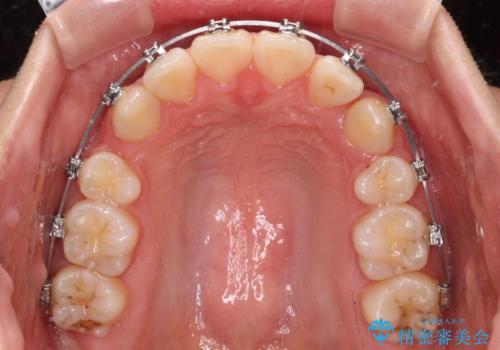

- メタルブラケット

上下ともに歯列が前方に突出していたため、上下左右の第一小臼歯4本を抜去する方針(既に上顎は抜歯されています)で、ワイヤー装置による矯正治療を行うこととしました。

舌の突出癖による影響もあったため、舌のトレーニングを並行して実施しました。

舌の突出癖があり、咬合力も強かったため、治療期間は長くなることが懸念されましたが、舌のトレーニングをしっかりと行っていただいたこともあり、2年弱で治療を終えることができました。